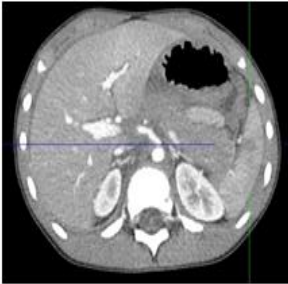

The case report is about a 7 years old boy, he was brought by ambulance accompanied by his father, who gave heteroanamnestic data regarding the child. Injury was caused during skiing by a direct collision from another person. On that occasion, he suffered head, abdomen and left lower leg injuries.Heteroanamnesis has indicated that after a collision with another skier, boy lost consciousness and had nausea. Blood pressure was 70/40 mmHg at the moment of arrival to hospital. At the time of examination he was conscious, communicative, oriented, did not reconstruct events, vomited twice, had nausea. The skin was pale. Abdomen was at chest level, tense, painful during palpation. Based on diagnostics (CT of the head, spine, pelvis with hips, thorax, abdomen, X-ray of lungs and left lower leg) as well as the laboratory findings (HTC 0.24, HGB 98) . CT showed a grade III spleen injury with a torn spleen greater than 3 cm and a hematoma with an irregular hypodense surface with obscure edges. The kidney had an irregular defect of the renal parenchyma deeper than 1 cm. The renal collecting system was not affected. This was considered grade III kidney damage. Free intraabdominal blood has been seen.(Figure 1.2.3).

Figure 1: The obtained CT scans show that the liver is inhomogeneous parenchyma with visible laceration that is monitored from segment IVa with the incision to the right lobe and propagated to the cholecyst lodge and in that part is presented as a hematoma and followed to the segment V where some free fluid is also observed.

Figure 2: Transection of the spleen in the lower pole and hematoma in the central part of a towards the lower pole. The hilus of the spleen appears intact.

Figure 3: Edema of the jejunum in the left hemiabdomen. Discrete inhomogeneity of the lateral arm of the left adrenal gland and pancreas tail edema most likely by type of contusion The CT finding on other organs of the abdomen was unremarkable except of free bulky fluid consist with haemorrhage in abdomen and pelvis.